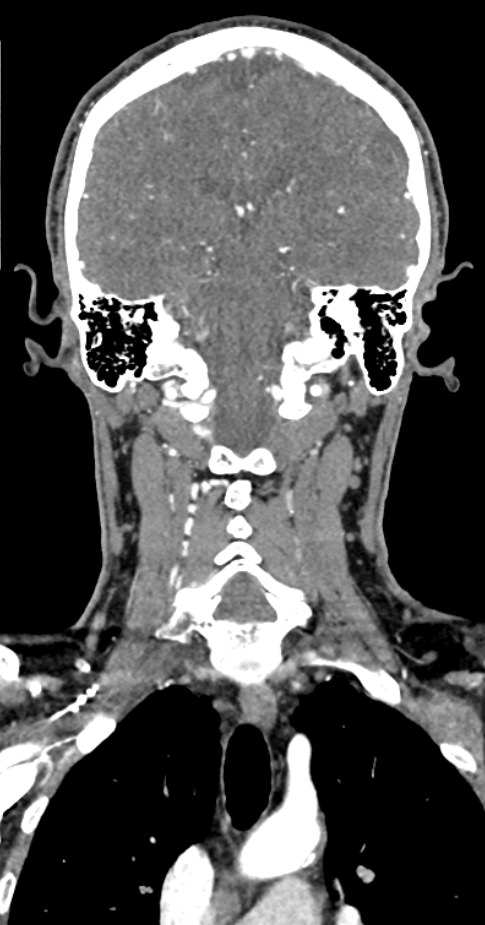

КТ сосудов шеи и головного мозга (КТ-ангиография) позволяет комплексно оценить состояние брахиоцефальных артерий и сосудов головного мозга, включая Виллизиев круг, передние средние и задние мозговые артерии. С помощью КТ-ангиографии можно выявить аномалии развития сосудов (в том числе, аневризмы артерий головного мозга, артериовенозные мальформации), патологические извитости, участки сужения и полной закупорки просвета сосуда. КТ-ангиография покажет утолщение стенки артерии, точную локализацию атеросклеротической бляшки, стенозы и окклюзии просвета сосудов, степень функционирования Виллизиева круга, что бывает особенно важно при планировании оперативного вмешательства и для оценки эффективности хирургического лечения.

В нашей клинике КТ сосудов шеи и головного мозга выполняется на современных мультиспиральных компьютерных томографах экспертного уровня TOSHIBA AQUILION. Для визуализации сосудистой системы в обязательном порядке проводится контрастное усиление. Для этого в вену пациенту вводится йодсодержащий контрастный препарат, который хорошо поглощает рентгеновские лучи и обеспечивает яркую видимость сосудистой сети на фоне окружающих тканей.

Высокотехнологичное оборудование последнего поколения обеспечивает высокую точность и контрастность изображений, благодаря чему получаются снимки и трехмерные модели сосудистой системы высокого качества. Увеличенное количество детекторов позволяет производить одномоментно множество послойных снимков, что значительно сокращает время исследования и минимизирует уровень лучевой нагрузки на организм пациента.